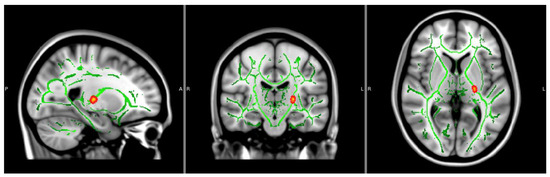

| FA Values | Voxels | MAX | MAX X (vox) | MAX Y (vox) | MAX Z (vox) |

| 22 | 0.95 | −23 | −19 | 2 | |

| OD Values | Voxels | MAX | MAX X (vox) | MAX Y (vox) | MAX Z (vox) |

| 39 | 0.958 | −16 | −11 | −5 | |

| 27 | 0.962 | −16 | −5 | 5 | |

| 17 | 0.956 | −21 | −16 | 1 |